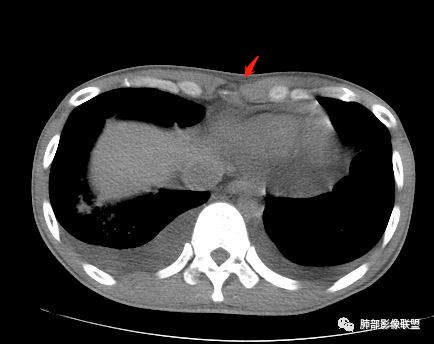

红星:病史资料:患者男,30岁,因“双小腿及双踝双足浮肿1周”入院。患者1周前无明显诱因下感双小腿及双踝双足浮肿,胸部CT示:两肺多发感染。尿酸增高,肝功能损害,两肺多发的结节状及片状的模糊阴影,小叶中心分布为主,病灶中心密度比较高,周围密度较淡,晕征,整体病灶比较单一,以渗出为主,两下肺分布,尤其是右下肺分布为甚,两侧胸腔积液,心包积液。心脏左心室明显增大。考虑肺部感染或者是血管炎的一些病变。个人认为,左心功能不全合并有肺水肿或者是血管炎的一些病变。

双侧胸水

心包积液

双侧胸腔积液,双下肺斑片状磨玻璃密度影,背景是大片状磨玻璃密度影,密度稍低一些。这个磨玻璃影非常弥漫,没有受局限,胸膜下不是很清楚,内部结构显示清楚,稍实变的区域也是,小叶间隔增厚,中轴间质也增厚。有些病变边缘有收缩,有轻度OP样特点,但是这些病变似乎密度非常均匀。

出血有可能,还要考虑到肺水肿,因为有胸腔和心包积液,小叶间隔也增厚。